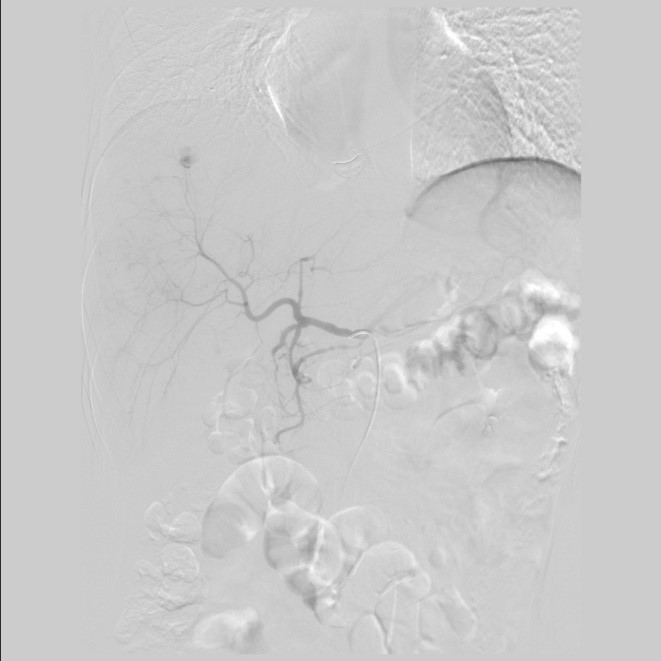

РЕЗУЛЬТАТЫ. Статистически значимых различий по полу, возрасту, механизму и тяжести травмы (по шкалам ISS, Ю. Н. Цибина, ВПХ-П) и тяжести состояния (ВПХ-СП) между пациентами групп не выявлено. Более половины (52,3 %) пострадавших основной группы пролечено без оперативных вмешательств на органах живота. При использовании предложенного алгоритма у пациентов со стабильной гемодинамикой лапароцентез уступил место менее травматичным и более точным методам диагностики внутрибрюшных кровотечений. Все лапаротомии в основной группе были выполнены по поводу других повреждений органов живота. У пострадавших обеих групп видеолапароскопия носила диагностический характер. Одному пациенту основной группы с повреждением печени IV степени по шкале AAST с продолжающимся внутрипаренхиматозным и внутрибрюшным кровотечением проведен эндоваскулярный гемостаз.

2. Рис 2.1

Тема

Тип Исследовательские инструменты

Посмотреть (91KB)

Метаданные ▾